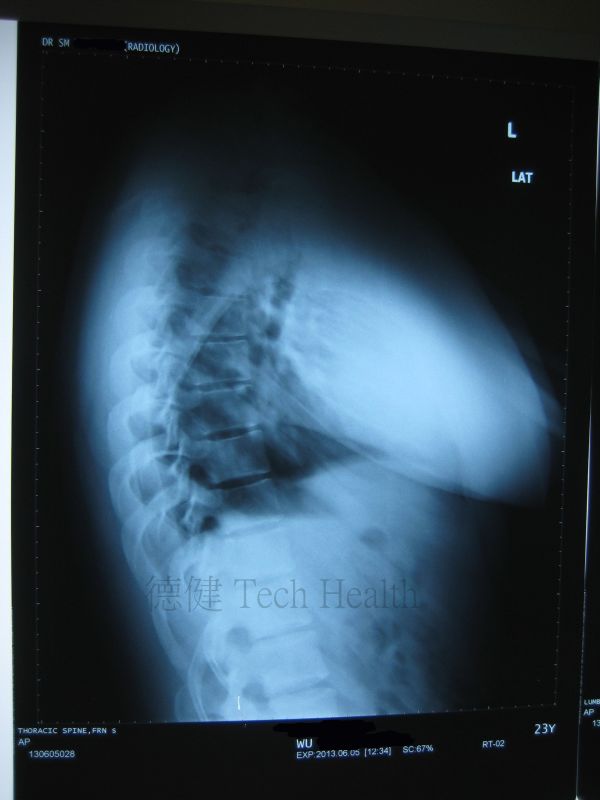

個案一 - 胡先生 23歲 - 肱二頭肌肌腱炎

- 2013-8-2 患者因長期參與投擲動作運動,過度使用肱二頭肌長頭而造成的重複性損傷,造成肌腱及其腱鞘受損與發炎。現見頸背拘緊,右肩關節前方疼痛,疼痛集中於結節間溝,時向遠端放射至肱二頭肌肌腹。腰亦有酸痛不適及肌肉拘緊。